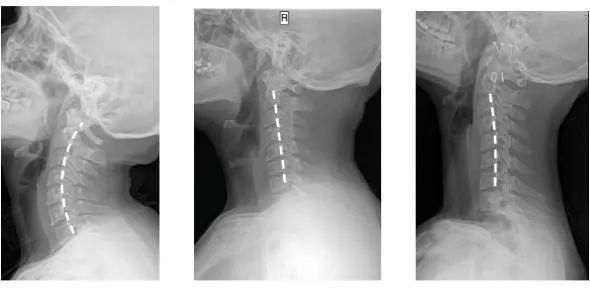

仰睡保持颈部「自然生理弯曲」

告别落枕,防治颈椎疾病

在中国,1.5亿人患有颈椎病

而90%的颈椎问题

都是因为

维持一个不正确的姿势时间太长引起的

人正常的颈椎是有弧度的

大约是前凸30-45°

但随着颈椎长时间承受着巨大压力

过于劳累状态

于是弧度就

逐渐退化 变直 甚至反弓

第一张为正常生理曲度,第二张曲度变直,第三张是反向弯曲

前凸的颈椎曲度被改变

结果就是引发椎间盘突出

造成对血管和神经的压迫

肩膀和脖子容易酸痛僵硬

这已是颈椎病的初期症状